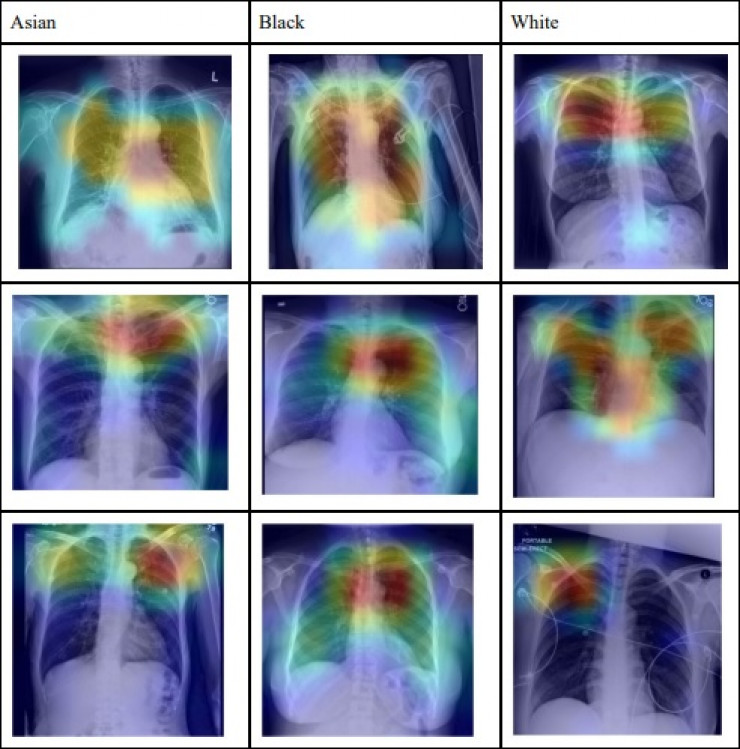

Доказательства того, что алгоритм может считывать расу с медицинских снимков человека, появились из тестов на пяти типах изображений, используемых в радиологических исследованиях. На снимках были изображены пациенты, которые идентифицировали себя как чернокожих, белых и азиатов.

Сообщается, что алгоритмы системы при определении обращают внимание, в частности, на разницу в физических характеристиках представителей разных рас. Кроме того, она анализирует снимки на перенесенные человеком заболевания, чернокожие, например, чаще болеют диабетом.

Ученые отметили, что ранее не считали расовую принадлежность человека, которая не является биологической категорией, видимой на снимках. Однако теперь, по данным авторов технологии, это можно сделать благодаря нейросети, так как точность ее определения достигает 80-99 процентов.